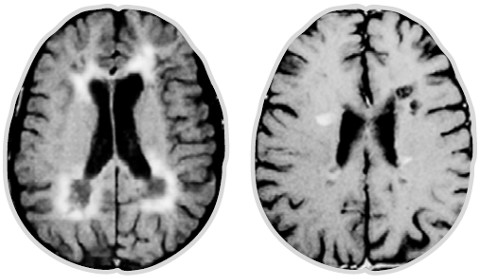

Рассеянный склероз (РС) – это хроническое, демиелинизирующее заболевание, в основе которого лежит комплекс аутоиммунно-воспалительных и нейродегенеративных процессов, приводящих к множественному очаговому и диффузному поражению центральной нервной системы, ведущее к инвалидизации и значительному снижению качества жизни.

Патогенез: аутоиммунное воспаление с последующей демиелинизацией и нейродегенерацией, в котором ключевую роль играет презентация аутоантигена В-клеткой, проникновение иммунных клеток через гемато-энцефалический барьер, высвобождение системно и локально в центральной нервной системе провоспалительных цитокинов иммунными клетками, выработка антител В-клетками и другие процессы.